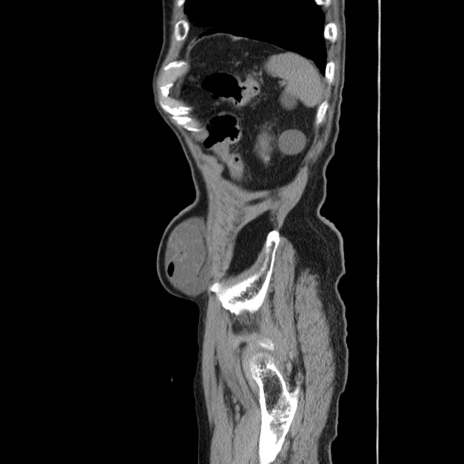

冠状断像